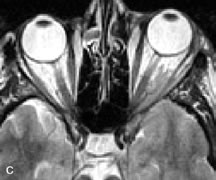

Muscle Disorders

Extraocular muscle enlargement in patients with thyroid-associated orbitopathy is demonstrated equally well with CT and MRI studies. However, the superior tissue contrast on MR images reveals better details of the relationships of the optic nerve to the thickened muscles at the orbital apex (Fig. 16).50 In addition, MRI may be able to differentiate between muscles that are enlarged as a result of edema and active inflammation and those enlarged because of fibrosis by their T2 relaxation times.21 Quantitative MRI was not found to be accurate in predicting the success of low-dose orbital irradiation.51 However, a muscular index relating the diameters of the rectus muscles to the bony orbital dimensions was useful in predicting optic nerve compression.52

Fig. 16. A-C, T1-weighted MR scans obtained with a high-resolution surface coil demonstrate fusiform enlargement of the extraocular muscles. The medial, lateral, and inferior rectus muscles are especially involved. Note the relative sparing of the tendinous insertions, a finding characteristic of this disease process, as well as fatty infiltration of the lateral and inferior rectus muscles. There is marked proptosis, best visualized on the sagittal image (A), and mild crowding of the optic nerve at the orbital apex.